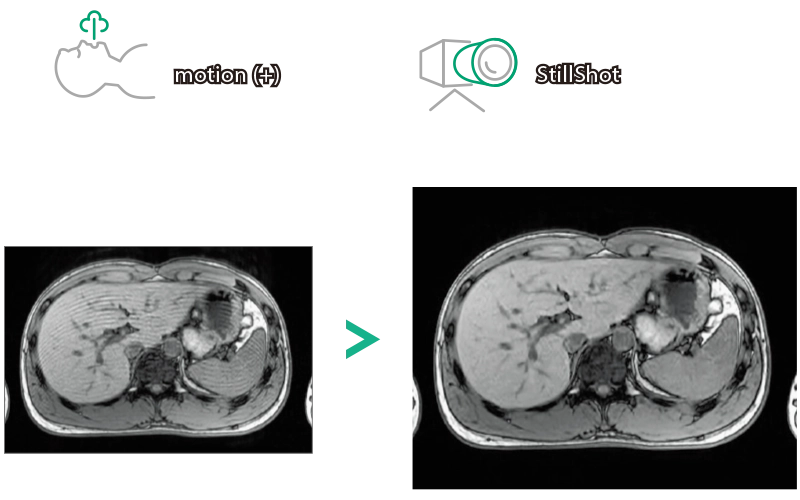

T1WI Dual Echo (Out) Breath hold

RADAR:Body movement suppression technology for those who cannot hold still

T2*WI RADAR, 2:34

T2WI FatSat Respiratory gating RADAR, 2:16